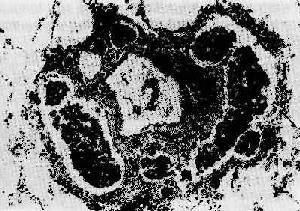

1)淋巴道转移:瘤细胞侵入淋巴管(图7-5)后,随淋巴流首先到达局部淋巴结。例如乳腺外上象限发生的乳腺癌首先到达同侧腋窝淋巴结;肺癌首先到达肺门淋巴结。瘤细胞到达局部淋巴结后,先聚集于边缘窦,以后生长繁殖而累及整个淋巴结(图7-6),使淋巴结肿大,质地变硬,切面常呈灰白色。有时有转移的淋巴结由于瘤组织侵出被膜而互相融合成团块。局部淋巴结发生转移后,可继续转移至下一站的其他淋巴结,最后可经胸导管进入血流再继发血道转移。

图7-5 肿瘤的淋巴道转移

肺内血管周围淋巴管扩张,充满瘤细胞团(瘤细胞栓子)